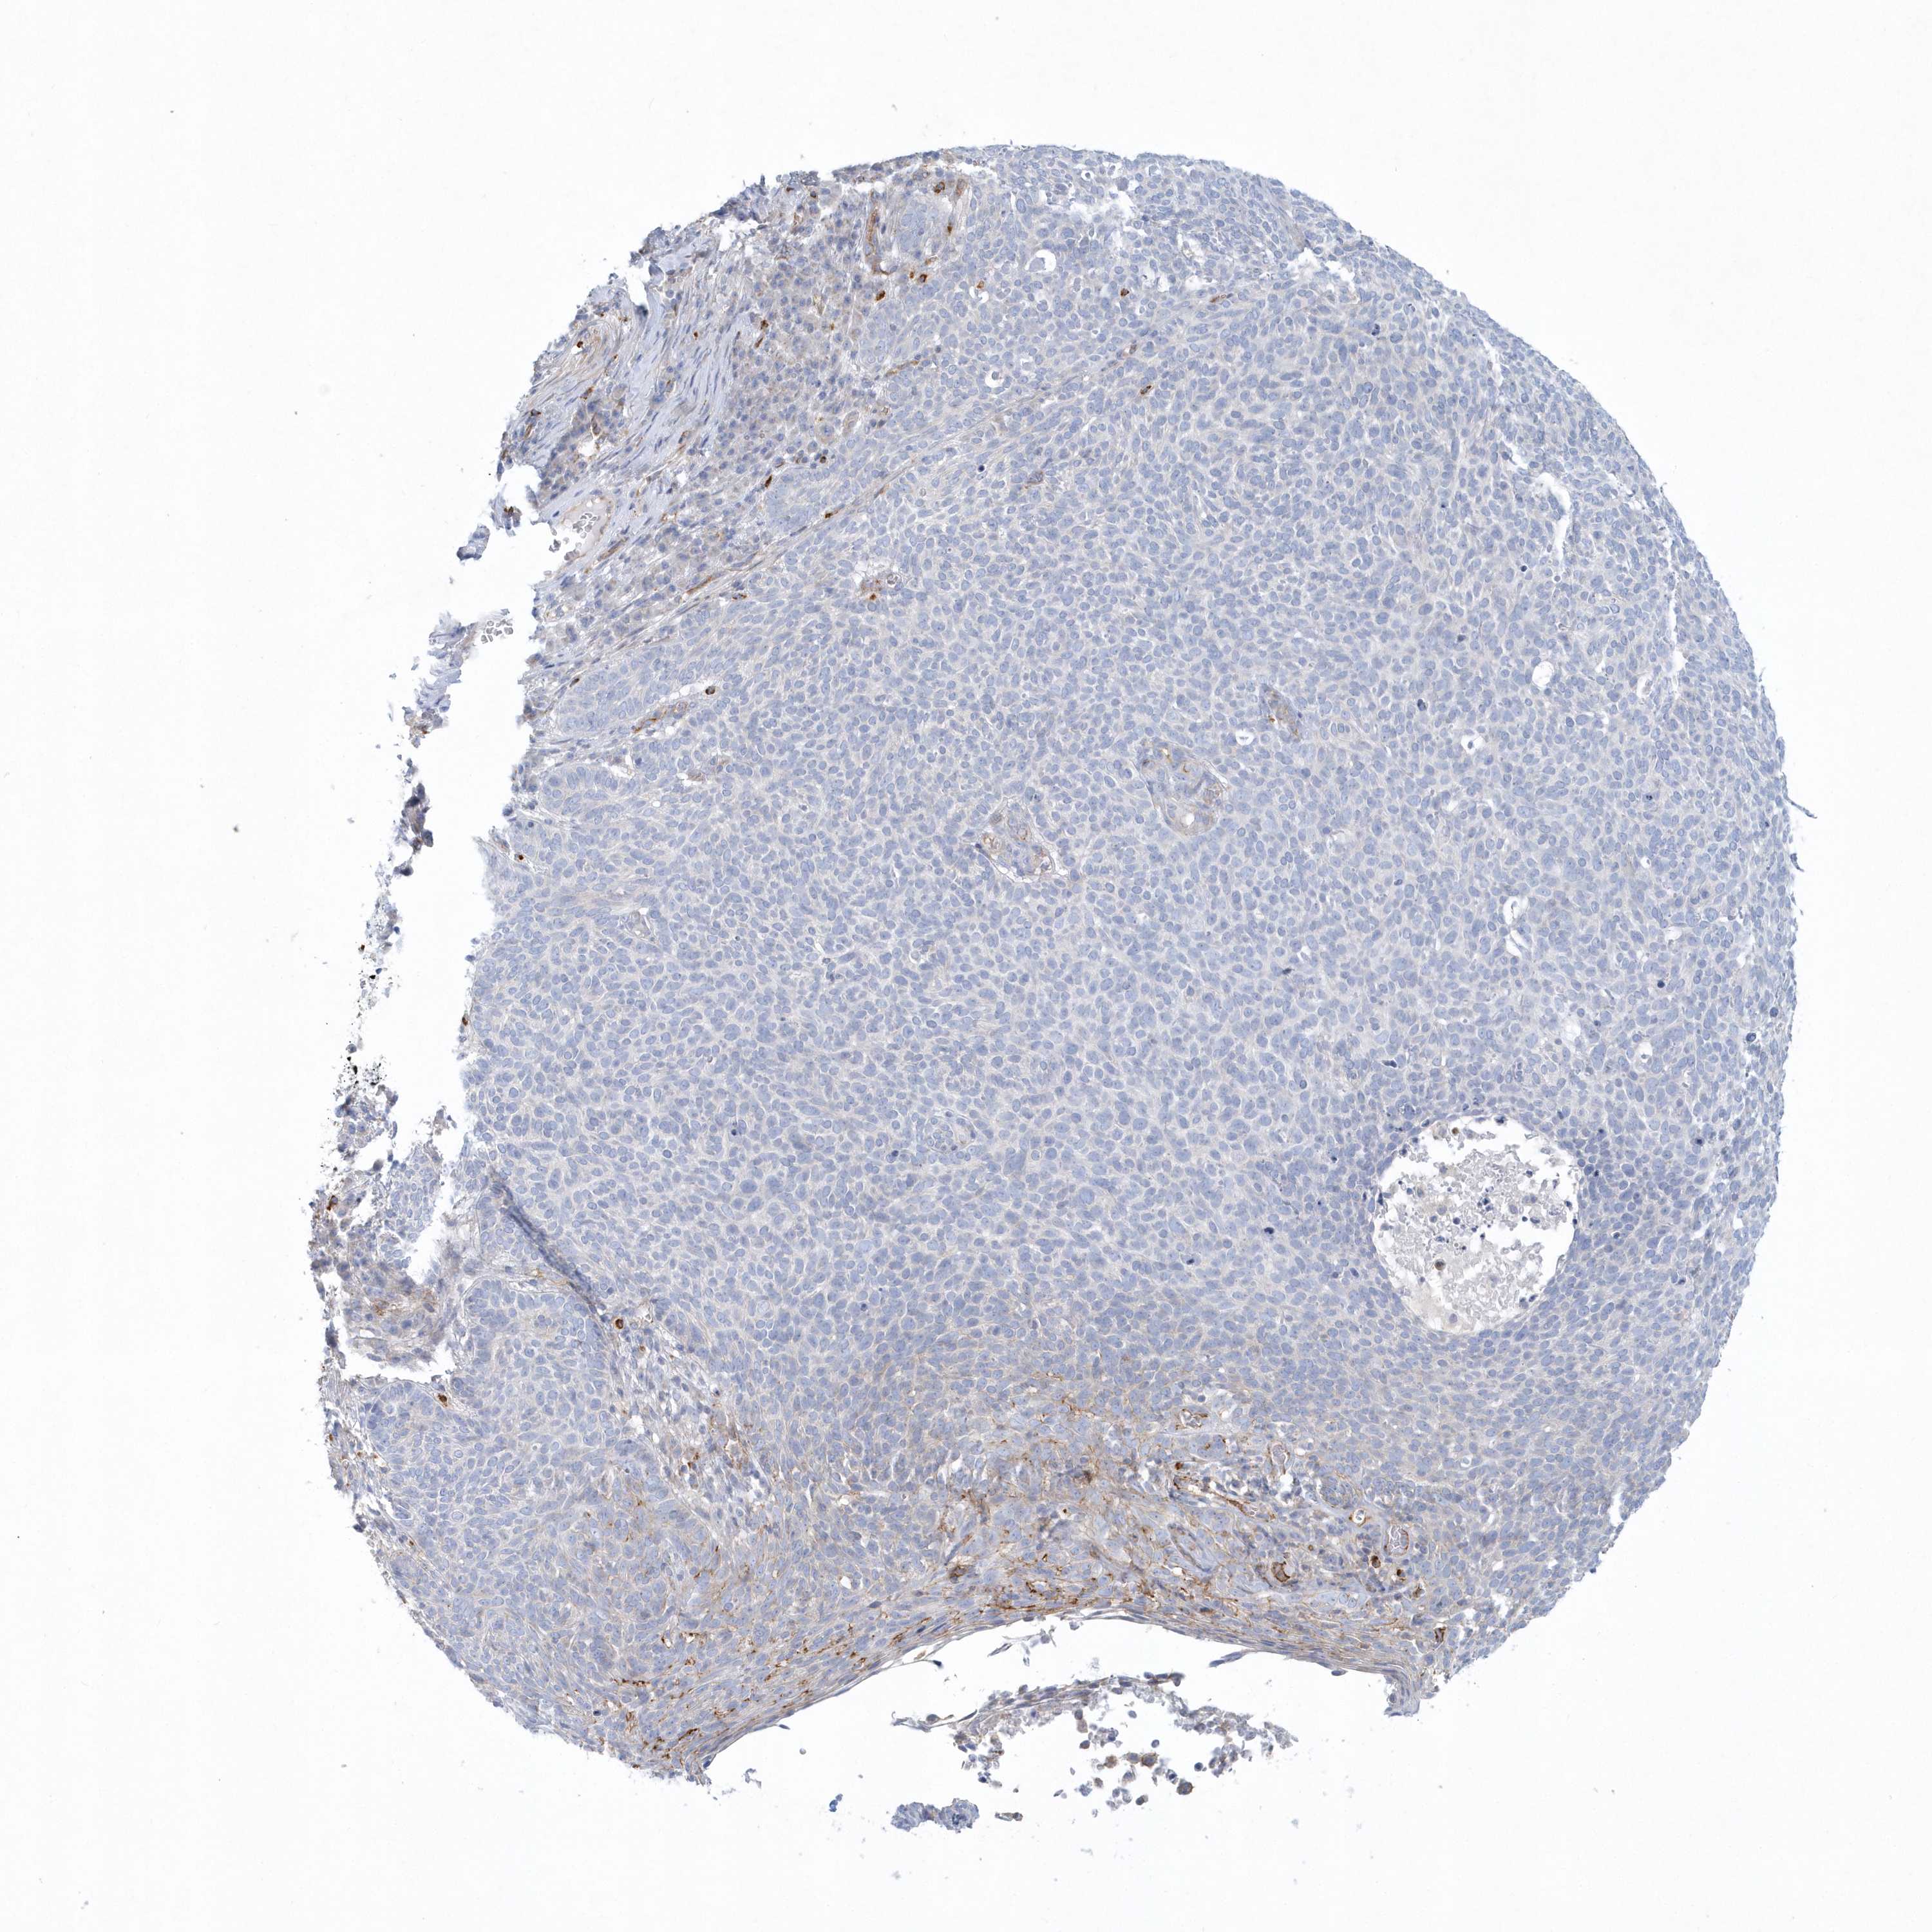

Basal cell and squamous cell cancer

SKIN CANCER - Protein expressioni

A mouse-over function shows sample information and annotation data. Click on an image to view it in a full screen mode. Samples can be filtered based on level of antibody staining by selecting one or several of the following categories: high, medium, low and not detected. The assay and annotation is described here.

Antibody stainingi

Antibody staining in the annotated cell types in the current human tissue is reported as not detected, low, medium, or high, based on conventional immunohistochemistry profiling in selected tissues. This score is based on the combination of the staining intensity and fraction of stained cells.

Each image is clickable and will lead to virtual microscopy that enables deeper exploration of all samples and also displays staining intensity scores, fraction scores and subcellular localization as well as patient and tissue information for each sample.

Antibody HPA036805

Antibody HPA036806

Staining

Low

Weak

75%-25%

Cytoplasmic/membranous

Squamous cell carcinoma, NOS